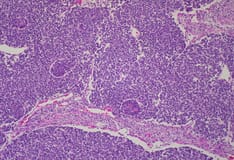

Images